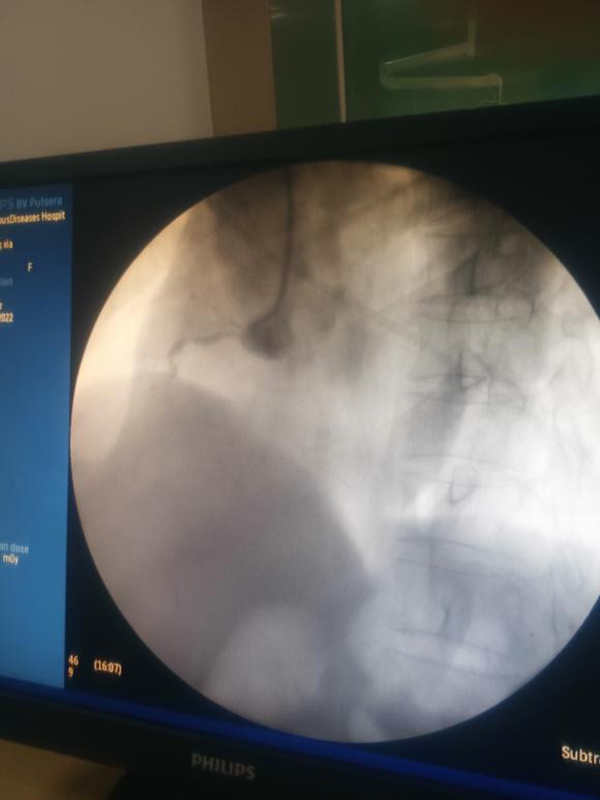

由于市傳染病醫(yī)院沒有DSA手術(shù)機房,僅有的一臺機器為非心臟介入手術(shù)所用,沒有心臟血管造影模式,且不能自動調(diào)整體位。徐通達(dá)主任與介入導(dǎo)管室技師王文友和護(hù)士李浩積極調(diào)試后,能夠基本滿足冠脈造影需要。同時,積極協(xié)調(diào)徐醫(yī)附院東院盡快準(zhǔn)備手術(shù)所用器械及搶救藥品送至市傳染病醫(yī)院。

按照疫情防控要求,所有參與手術(shù)人員均做好全程防護(hù),嚴(yán)格執(zhí)行防護(hù)措施。這樣給手術(shù)帶來極大的不便。為了做好充分準(zhǔn)備,術(shù)前,徐通達(dá)主任早早將洗手衣、鉛衣、防護(hù)服、面罩、手術(shù)衣穿戴整齊。術(shù)中,徐通達(dá)主任克服了患者耳聾、不?人缘炔荒芎芎门浜弦蛩,以及由于防護(hù)需要防護(hù)鏡產(chǎn)生水汽不能清晰讀圖及造影圖片不清晰等多重困難因素,依靠多年來積累下的經(jīng)驗,沉著冷靜,嫻熟精準(zhǔn)操作,抽吸血栓,球囊擴張,迅速開通患者閉塞的右冠狀動脈,植入1枚支架,血流恢復(fù)至TIMI 3級,ST段回落,血壓上升,生命體征逐漸平穩(wěn)。經(jīng)過徐醫(yī)附院醫(yī)護(hù)團(tuán)隊的共同努力,患者得到成功救治。